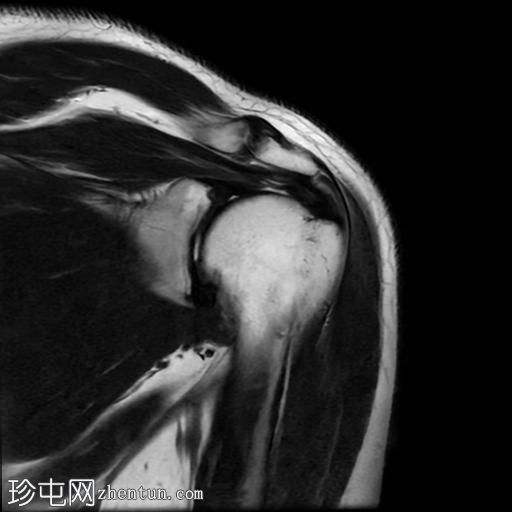

MRI

轴位PD序列

脂肪抑制序列

冠状位

T2加权像

T1加权像

冠状位PD序列

矢状位

PD脂肪抑制序列

冈上肌腱中后部关键区及肌腱止点纤维可见一低信号椭圆形病灶,大小约5 x 8 x 16 mm,提示钙化性肌腱炎。

肩锁关节轻度关节囊肥厚及退行性改变。

肩峰类型:II型